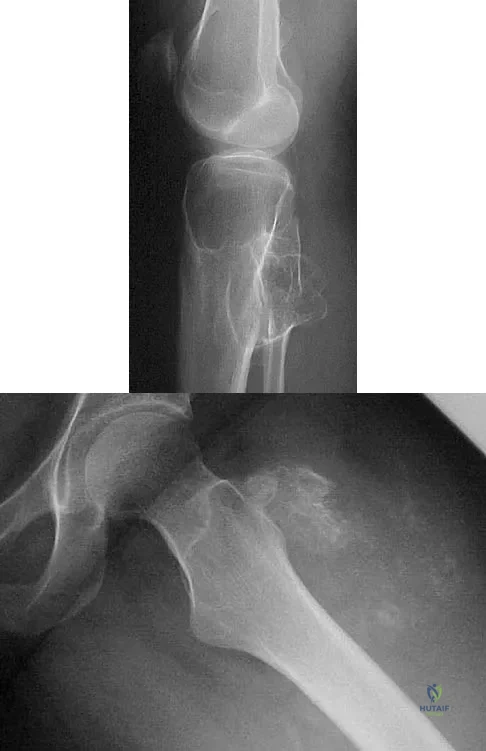

A 64-year-old man with a history of metastatic lung cancer reports increasing right hip pain over the period of several months. Radiographs are shown in Figures 3a and 3b. Initial management should consist of

Explanation